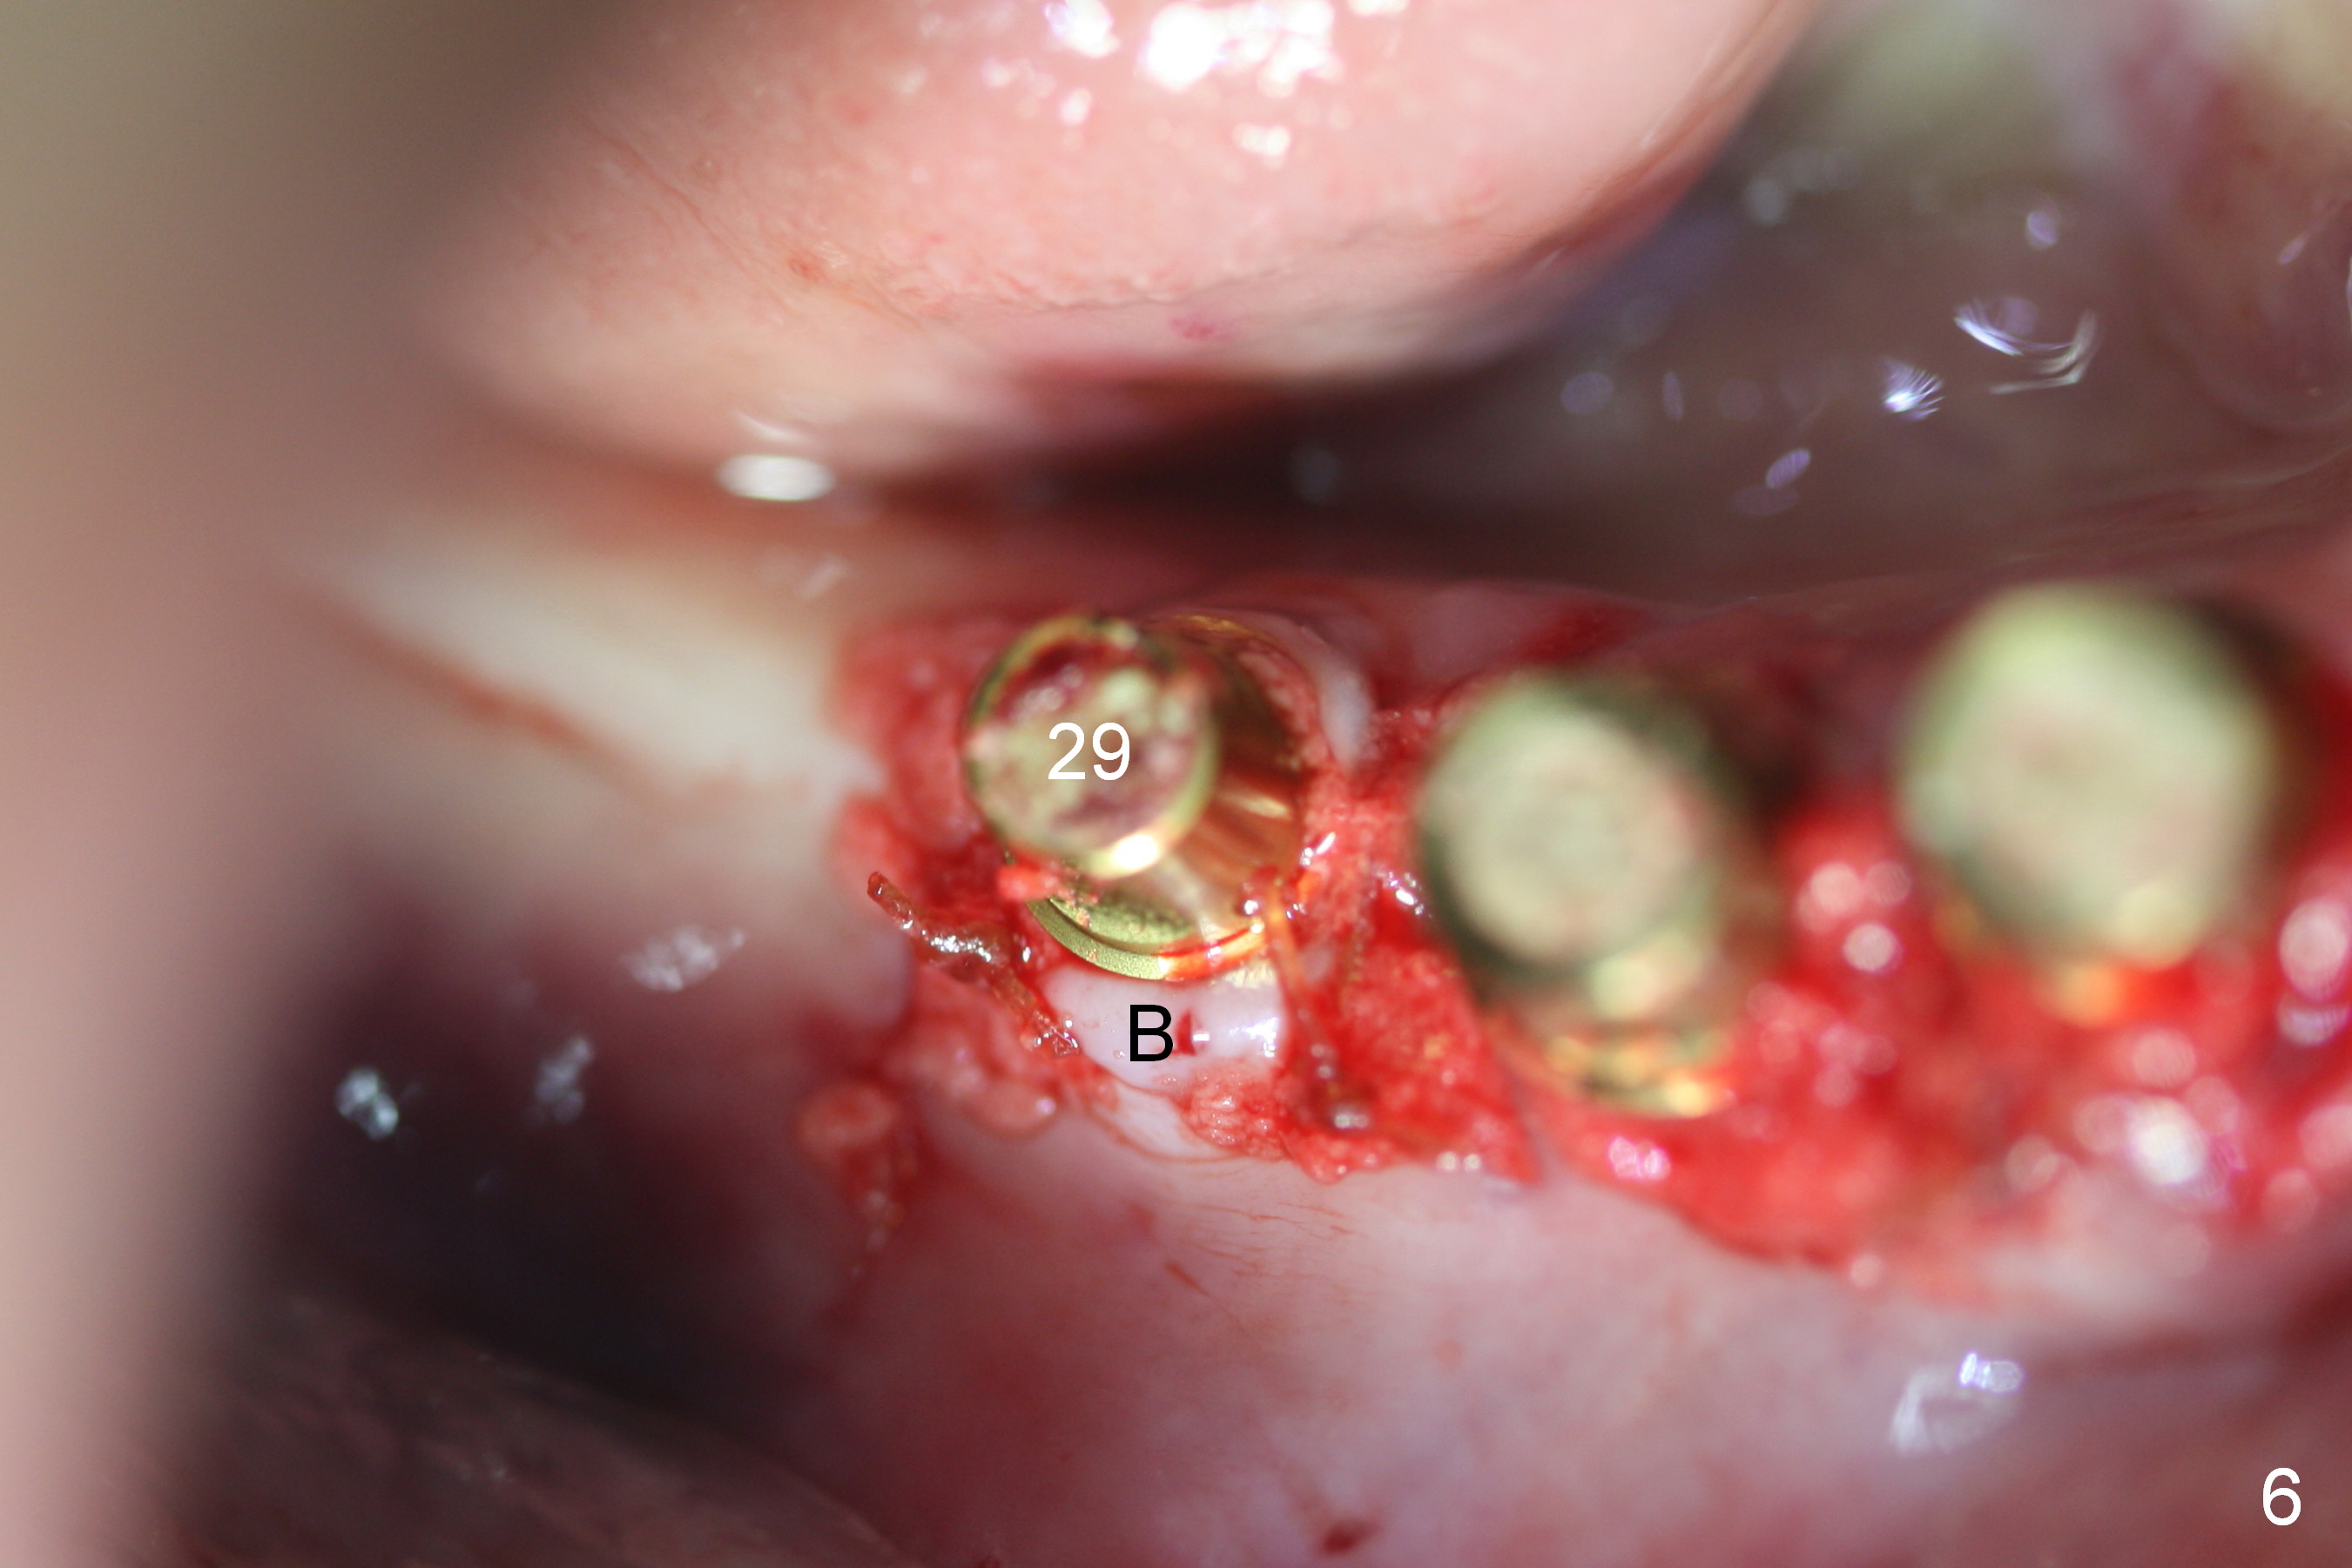

A 86-year-old man returns to office for the lower right quadrant reconstruction with implants. In addition to the immediate ones at the sites of #27 and 28 (Fig.1), how many and where else? The patient reveals that he does not plan to get an implant at the site of #3 (Fig.2). Therefore there is no need for an implant at #30. Preop CT shows that bone width is compromised at #26. So the 3rd site will be #29 (Fig.3,4). All of the 3 implants (4.5x14 mm, 4.5x12, and 4.1x12 mm) achieve primary stability (»55 Ncm). An immediate provisional could be provided, but it seems difficult to close the buccal (Fig.5 B) gaps of #27 and 28 after bone graft with the provisional. In contrast, the gingiva adapts to the implant at #29 well (Fig.6 B). Perio dressing is applied to the abutments (Fig. 7: #27-29), the edentulous space at #26 and the neighboring teeth (#23,24). It would be ideal to apply a non-resorbable membrane to the buccal opening at #27,28 (Fig.8 white line) prior to perio dressing placement. In case of dislodgement of the latter, the membrane is able to keep bone graft in place.